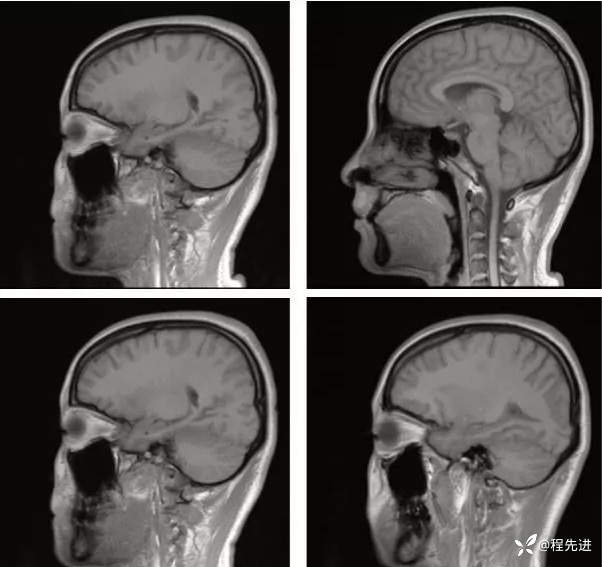

【神经】特别精彩病例|发热、头痛20天

主诉:发热、头痛20天

病史:患者20天前无明显诱因下出现畏寒、发热,热峰39.5℃,热型不规则,不伴咽痛,流涕,感头昏,有头痛,阵发性加剧,伴呕吐,为胃内容物非喷射性。患者在外院查头颅CT示:未提示异常。外院予以“头孢类、退热药”,无明显好转。我院急诊予以“泼尼松,热毒宁"治疗无明显好转